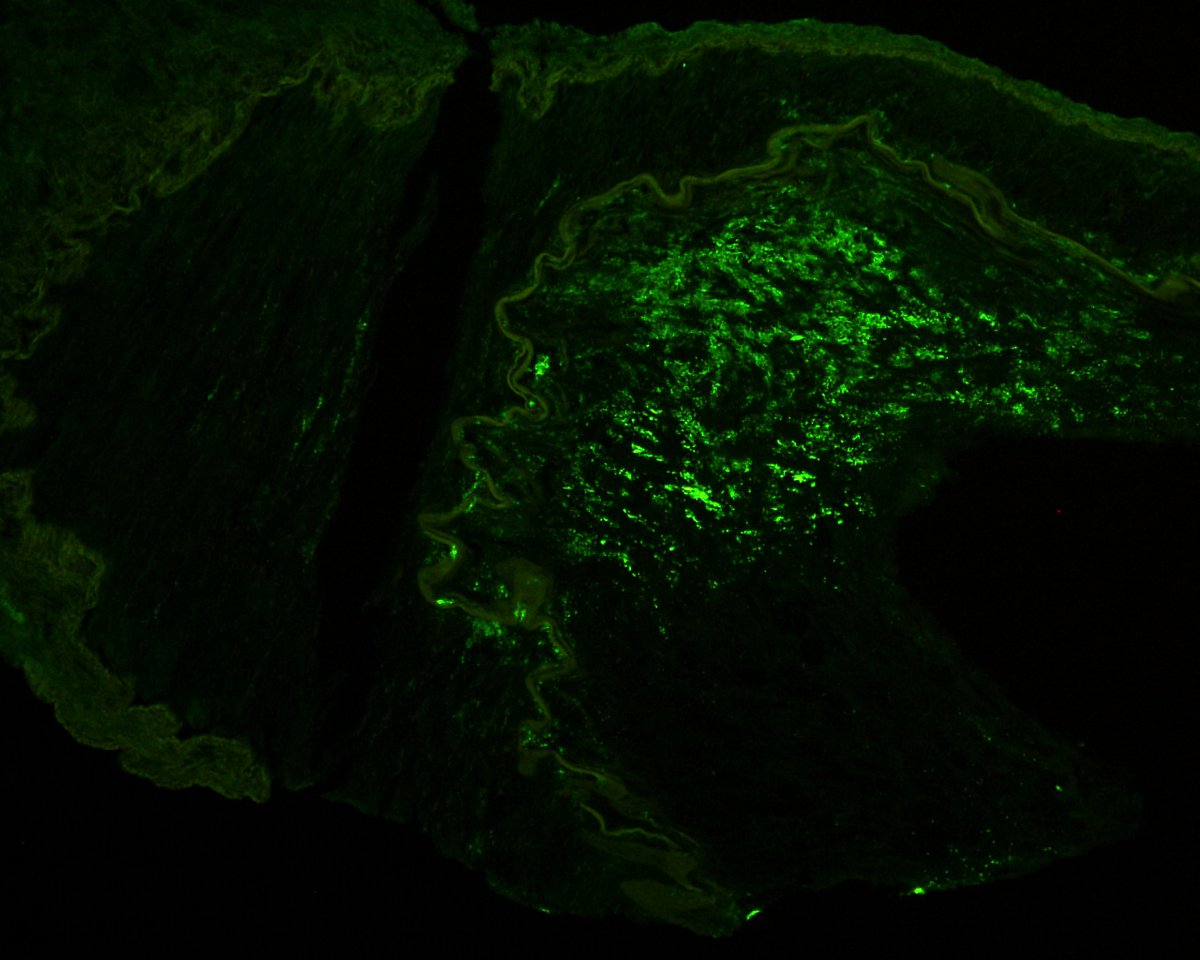

The Banff 2024 meeting report is official! Link to the article (free access) is below- now get ready for the next Banff meeting, October 5-9, 2026, in beautiful Banff, Alberta, Canada!!

authors.elsevier.com/sd/article/S16… @Renalpathsoc #renalpath